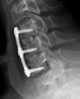

Bone grafting is a surgical procedure that replaces missing bone in order to repair bone fractures that are extremely complex, pose a significant health risk to the patient, or fail to heal properly. Some small or acute fractures can be cured without bone grafting, but the risk is greater for large fractures like compound fractures. [Source: Wikipedia ]